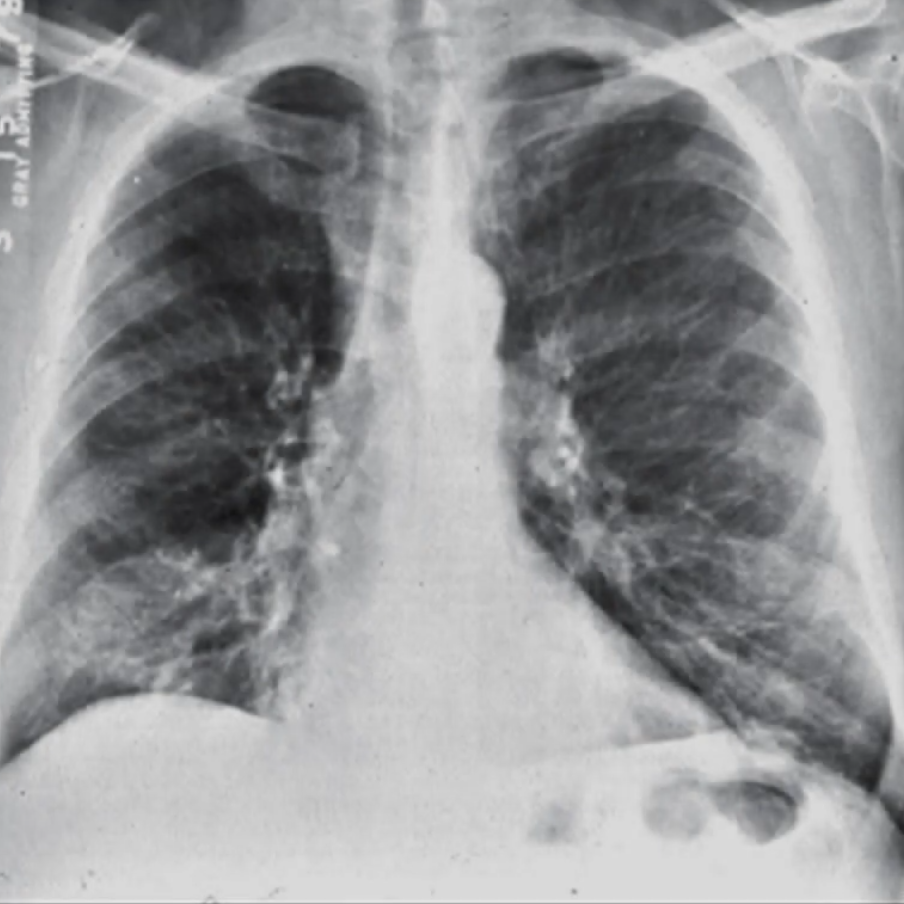

Interstitial Opacities

Further described based on pattern:

Differentials Predominantly reticular: idiopathic pulmonary fibrosis, connective tissue disorders (e.g. scleroderma, rheumatoid arthritis), atypical pneumonia, idiopathic interstitial pneumonia, asbestosis, chronic aspiration, pulmonary drug toxicity (e.g. nitrofurantoin), sarcoidosis, chronic hypersensitivity pneumonitis

Predominantly nodular:

- <2 cm: miliary tuberculosis, fungal infection, silicosis, sarcoidosis

- >2 cm: metastatic cancer, lymphoma, subacute hypersensitivity pneumonitis, granulomatosis with polyangiitis, rheumatoid nodules